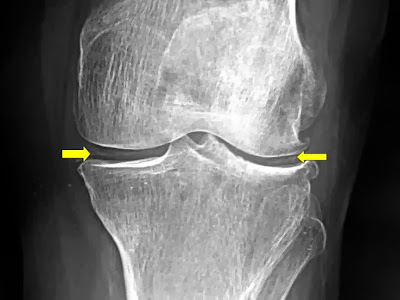

Chondrocalcinosis

X-ray will show characteristic chondrocalcinosis. (IMPORTANT)